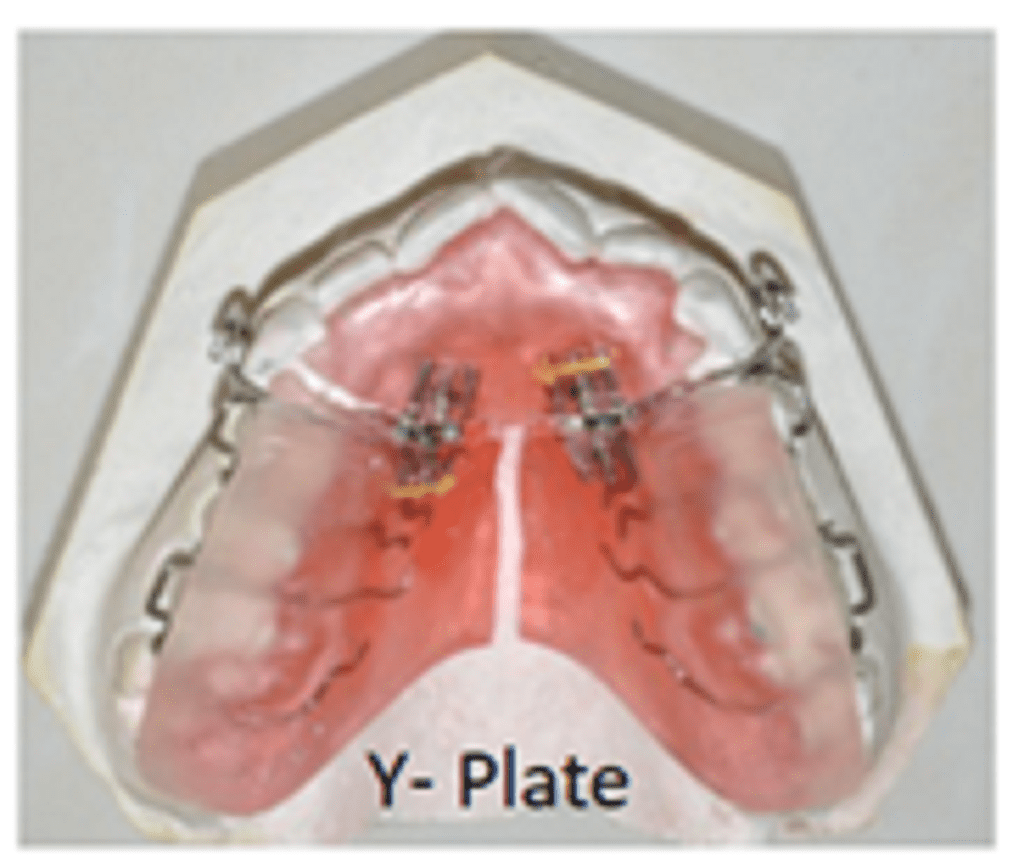

Modifications of expansion plate

Apart from the horizontal placement for transverse expansion, screws can be placed in the following ways:

- Screws are placed in the anterior aspect of the palate parallel to the mid-palatal suture for anterior expansion. E.g., cases of anterior crossbite.

- 2. A ‘Y’-shaped plate will produce simultaneous lateral expansion of posterior teeth and anterior expansion.

- Distalisation of buccal segments can be achieved using expansion screws.

- Expansion plates can be modified for asymmetric expansion.